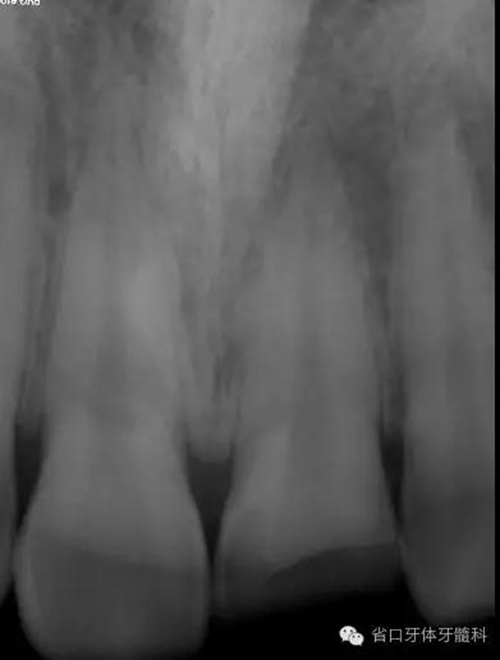

術(shù)前X線片

X線片示21冠折,根段未見(jiàn)明顯牙折影像。